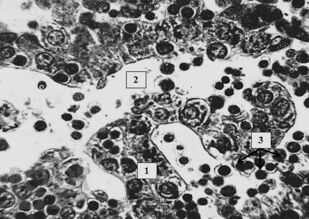

Монография посвящена функциональной морфологии и элементам общей патологии самой большой железы организма человека – печени. Подробно рассматриваются функции, развитие, строение и некоторые виды общей патологии печени, такие, как дистрофии, воспаление, некроз, нарушение кровообращения, склеротические процессы, регенерация и компенсаторно-приспособительные процессы, опухолевые процессы и др. Описываются изменения в печени при шоке, приведены сведения по трансплантации и биоинженерии печени. С учетом самых современных научных данных особое внимание уделяется стволовым клеткам печени и перспективам их использования в терапии печеночной патологии. В монографии широко используются собственные научные данные, причем подробно описаны и проиллюстрированы все стадии развития цирроза печени у лабораторных крыс. Подробно описана оригинальная легковоспроизводимая методика получения цирроза печени у этих животных, обычно представляющая затруднения для воспроизводства. Книга хорошо иллюстрирована высококачественными оригинальными цифровыми микрофотографиями.

В монографии на основе собственных данных проведено сравнение строения печени человека и крыс как в норме, так и при развитии цирротического процесса, что имеет большое значение для фундаментальных исследований. Монография предназначается для гистологов, патологоанатомов, судебных экспертов-гистологов, гепатологов и гепатотрансплантологов, а также магистрантов, аспирантов, преподавателей и студентов всех курсов лечебного и стоматологического факультетов высших медицинских учебных заведений